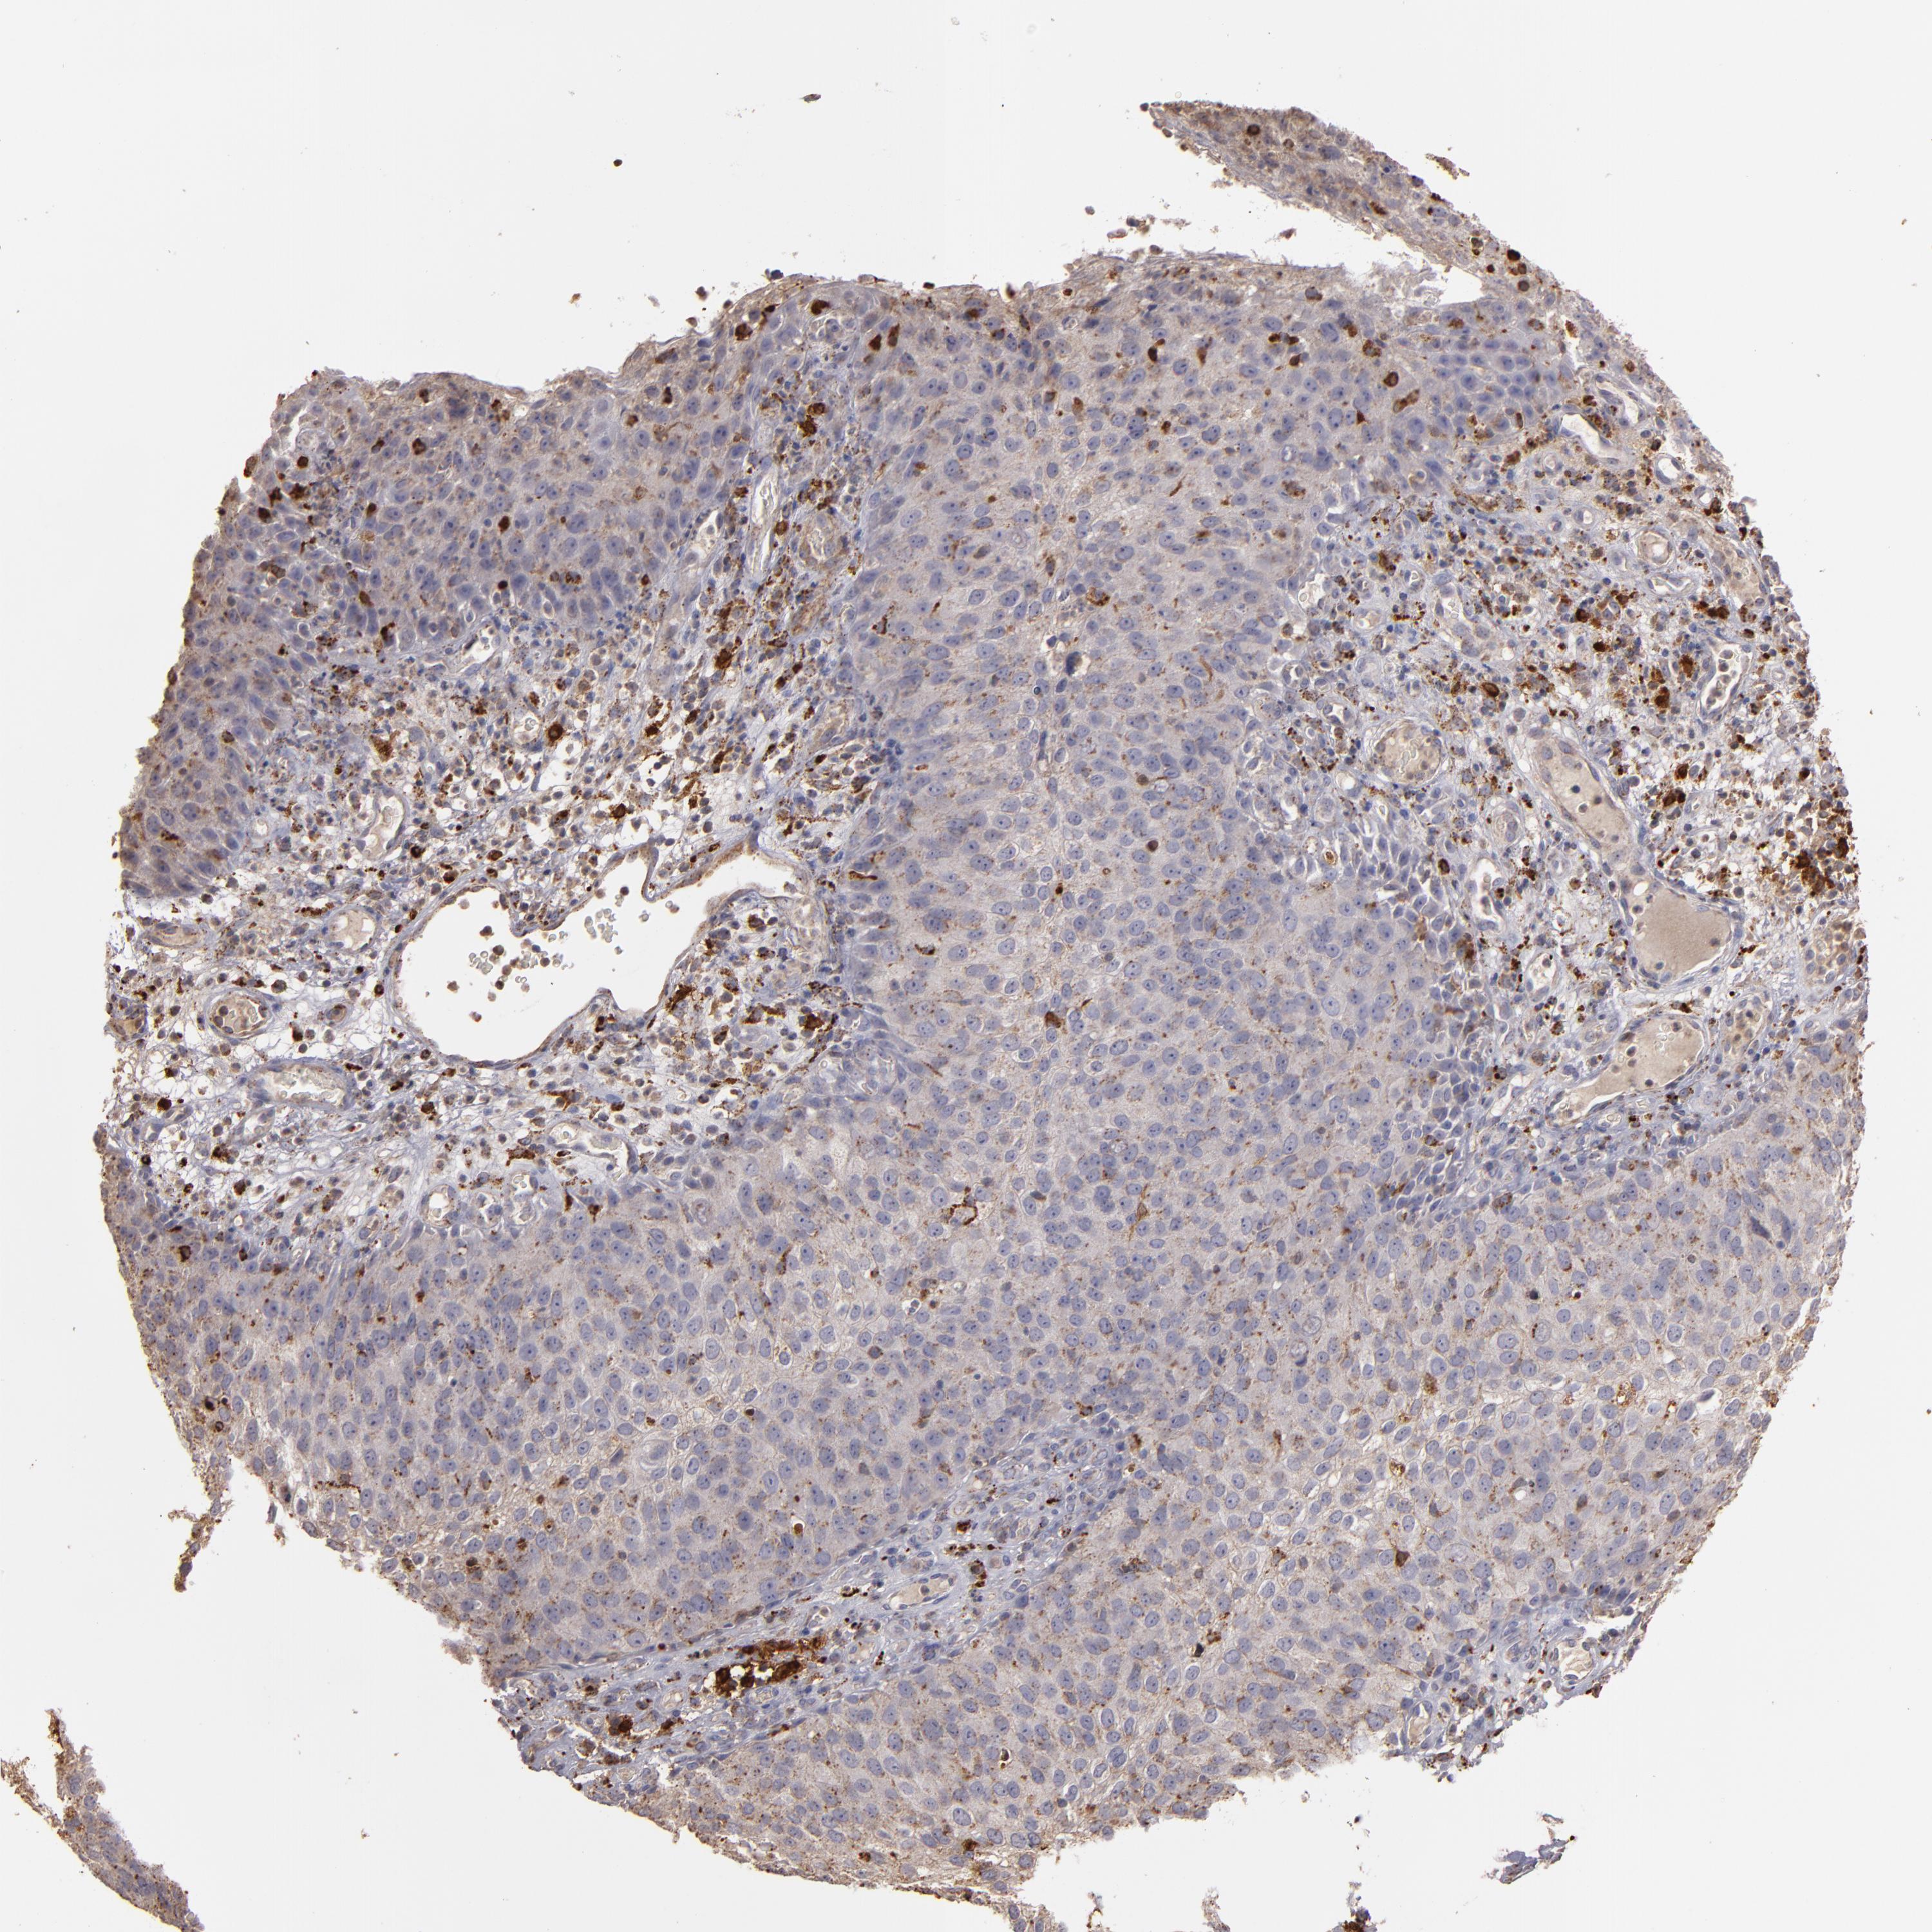

SKIN CANCER - Protein expressioni

A mouse-over function shows sample information and annotation data. Click on an image to view it in a full screen mode. Samples can be filtered based on level of antibody staining by selecting one or several of the following categories: high, medium, low and not detected. The assay and annotation is described here.

Each image is clickable and will lead to virtual microscopy that enables deeper exploration of all samples and also displays staining intensity scores, fraction scores and subcellular localization as well as patient and tissue information for each sample.

Antibody HPA001852

Antibody CAB009593

Squamous cell carcinoma, NOS

Basal cell carcinoma